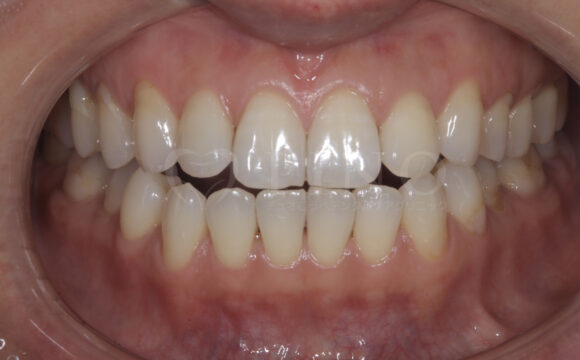

症例3:歯の黄ばみが気になる(20代女性)

主訴 歯の黄ばみが気になる 診断名 歯の内部の黄ばみ 原因 歯の内部の黄ばみ 治療期間 オフィスホワイトニング 7回 費用 ホワイトニング3ヶ月コース 116,000円 副作用・注意点 知覚過敏様症状が出る可能性がある 備考 ホームホワイトニング併用 -